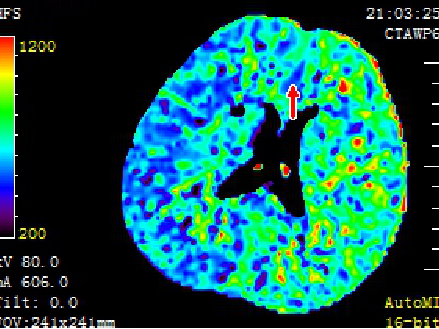

急诊予以静脉溶栓,同时完善头颈CTA+CTP、MIStar相关检查

结合CTA结果,提示左侧颈内动脉起始部至颈内动脉末端未见显影,起始部成鼠尾征改变,前交通动脉开放,双侧大脑中动脉显影良好。MIStar图像提示核心梗死灶和缺血半暗带较小,但是MTT提示左侧大脑中动脉流域区明显延长。